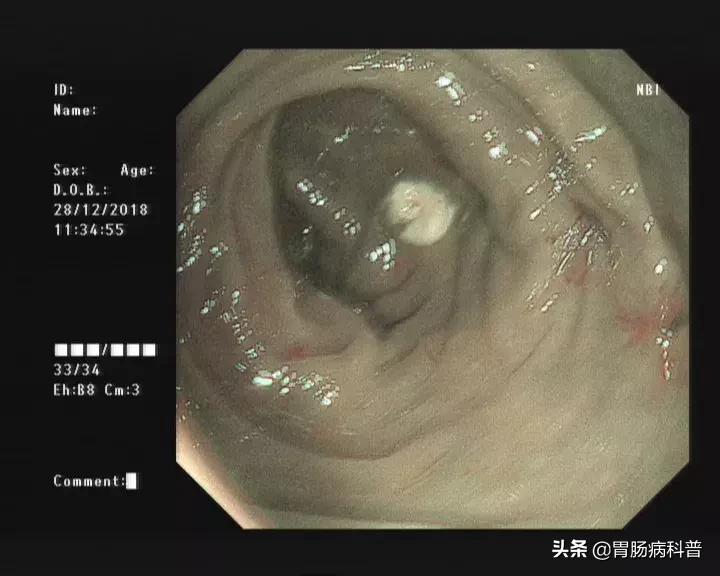

(下图可见白色脓液)

1.内镜下阑尾腔插管:

正常的阑尾开口部都被Gerlach’s瓣覆盖(如图,双箭头示Gerlach’s瓣);

通过内镜前端的透明帽的帮助下,推开Gerlach’s瓣(黄箭头),并进行阑尾腔插管。

当黄斑马导丝及导管置入阑尾腔时,可见脓性分泌物涌出。随之进行阑尾腔冲洗;